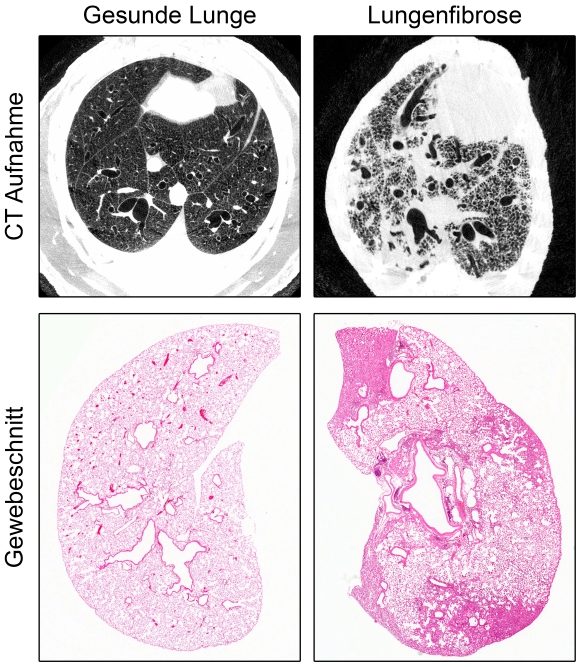

Dem Team um Prof. Dr. Marcus Mall, Direktor der Klinik für Pädiatrie mit Schwerpunkt Pneumologie, Immunologie und Intensivmedizin der Charité und Professor des Berlin Institute of Health (BIH), ist es zusammen mit Forschenden des Deutschen Zentrums für Lungenforschung (DZL), des Universitätsklinikums Heidelberg und des Deutschen Krebsforschungszentrums nun erstmals gelungen, ein Tiermodell zu entwickeln, das die sogenannte idiopathische pulmonale Fibrose (IPF) detailliert widerspiegelt. Da NEDD4-2 für die frühe Entwicklung unverzichtbar ist, wurde das kodierende Gen erst bei erwachsenen Tieren gezielt in der Lunge entfernt. Die Wissenschaftler und Wissenschaftlerinnen untersuchten diese dann zu einem späten Zeitpunkt, der etwa der Diagnosestellung beim Patienten entspricht. Dabei zeigten Messungen der Sauerstoffsättigung eine für die Erkrankung typische Verschlechterung der Lungenfunktion. Durch Gewebeschnitte und Bildgebung der Lunge mittels Computertomographie ließen sich außerdem die strukturellen Kennzeichen einer Fibrose wie eine fleckige Vernarbung nachweisen. Die Bedeutung von NEDD4-2 bei der Krankheitsentstehung von IPF zeigt sich auch daran, dass sowohl die Transkript- als auch die Proteinmenge in Lungenbiopsien von Patienten stark reduziert ist. Außerdem ergab eine Untersuchung des Proteomprofils, also der Gesamtheit aller Proteine, mittels Massenspektrometrie eine hohe Übereinstimmung an Proteinen, die sowohl bei Patienten mit IPF als auch im Tiermodell eine veränderte Expression aufweisen. „Unsere Erkenntnisse können dazu beitragen, die Entstehung und den Verlauf der Lungenerkrankung weiter zu untersuchen und neue Therapien zu entwickeln, beispielsweise können Substanzen, die für eine Therapie infrage kommen, in einem präklinischen Stadium erprobt oder eine Früherkennung der Erkrankung ermöglicht werden“, sagt Prof. Mall.

Abbildung: Schwere Lungenfibrose im Tiermodell: In computertomographischen (CT) Aufnahmen und in Gewebeschnitten ist zu erkennen, dass gesundes, luftgefülltes Gewebe durch verdicktes Bindegewebe ersetzt wird.